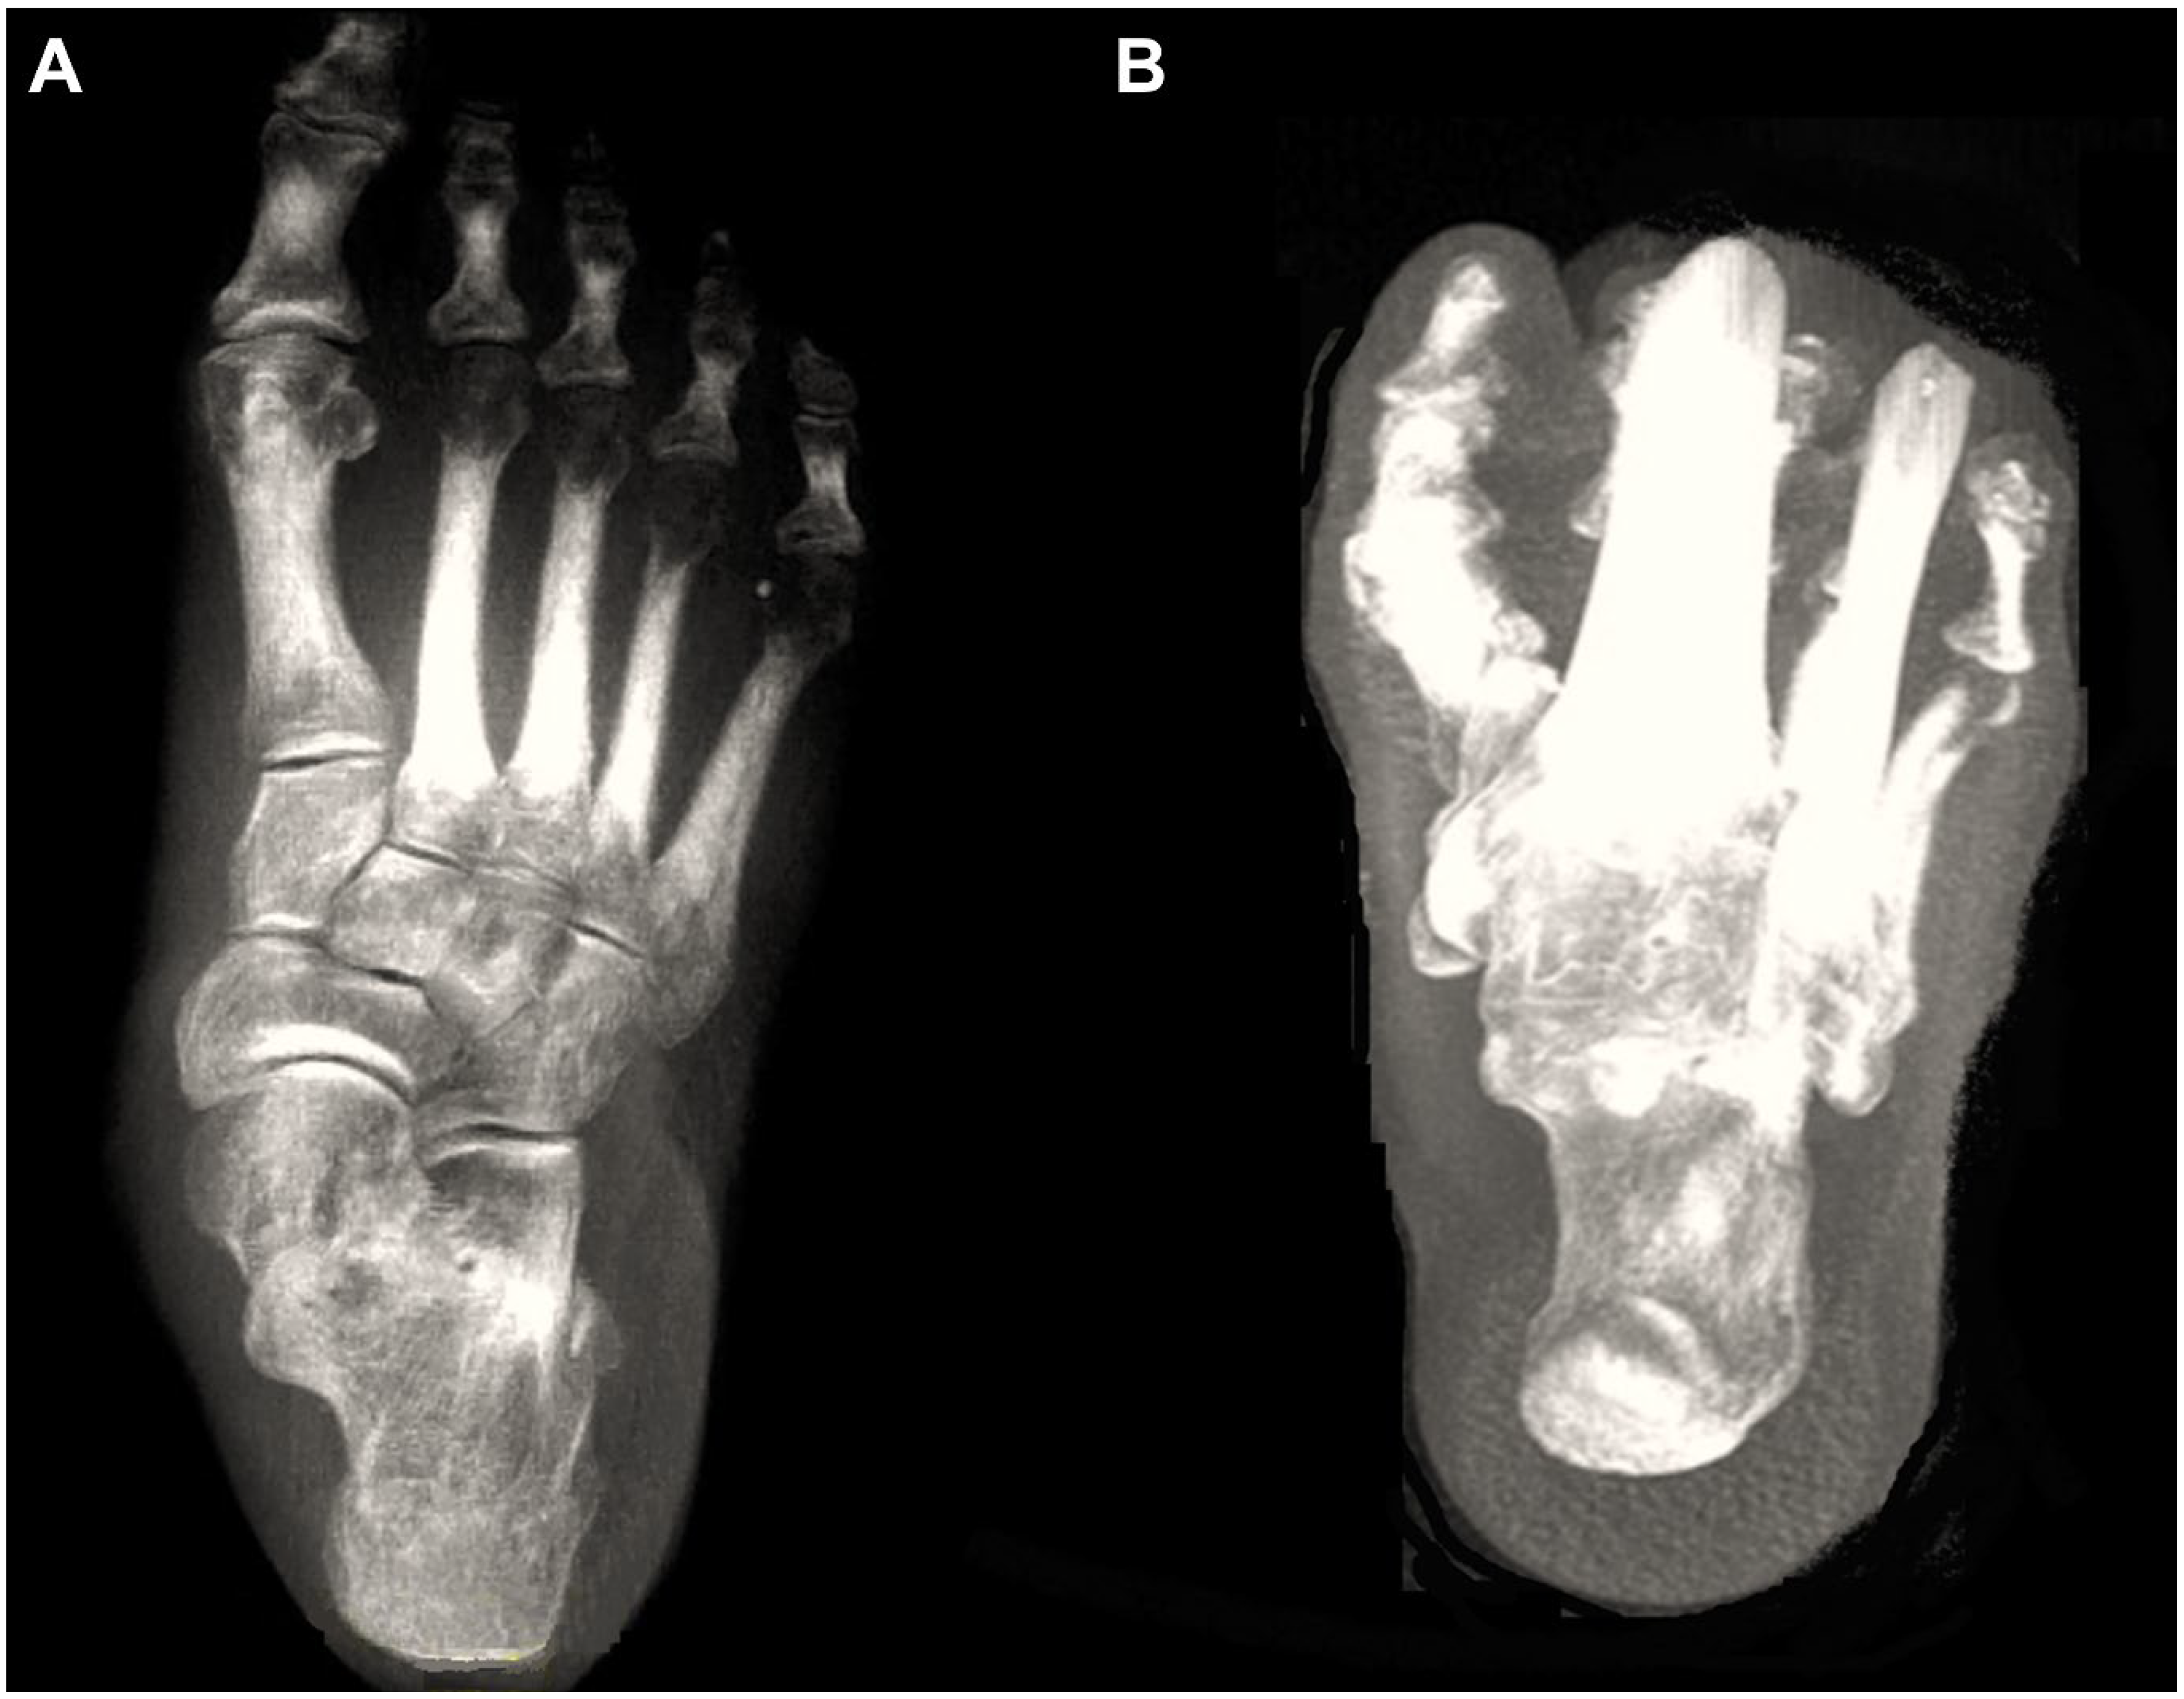

Figure 1.

Digitally reconstructed radiographs (DRRs) demonstrating foot anteroposterior (A) and hindfoot alignment (B) views.